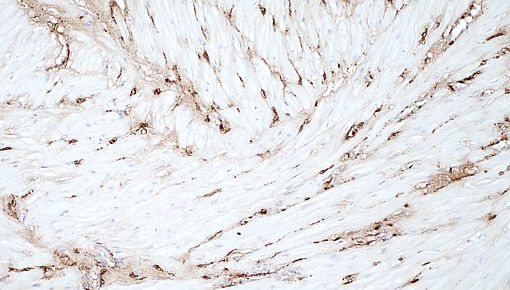

Die wachsende Zahl der Entbindungen per Kaiserschnitt stellt die Geburtsmedizin vor eine neue Herausforderung: Wie kann eine vollständige Regeneration der Gebärmutterwunde erreicht werden? Eine mangelhafte Reparatur und die daraus resultierende Narbenbildung stellen ein hohes Risiko für Endometriose, Unfruchtbarkeit oder, im Falle einer späteren Schwangerschaft, für eine abnorm invasive Plazentation dar. In unserem Labor befassen wir uns interdisziplinär mit dieser Herausforderung, und zwar an der Schnittstelle zwischen dem Immunsystem und der Wundheilung in der Geburtshilfe. Wir stellen die Hypothese auf, dass die drastischen Veränderungen des Uterusimmunsystems, die durch die Wehen ausgelöst werden, die Regeneration der Wunde begünstigen. Im Gegensatz dazu kann eine Störung der Immunreaktionen bei ausbleibenden Wehen die Heilung der Gebärmutter behindern, was zu einer Narbenbildung an der ehemaligen Kaiserschnittwunde führt. Um diese Hypothese zu prüfen, wollen wir einen räumlich-zeitlichen Überblick über die Interaktion zwischen dem Immunsystem und dem Wundheilungsprozess der Gebärmutter nach wehenbedingten vaginalen bzw. Kaiserschnitt-Entbindungen bei Mäusen und menschlichen Geweben erstellen. Auf der Grundlage dieses Wissens erwarten wir, dass Maßnahmen zur Wiederherstellung optimaler Bedingungen für die Regeneration der Gebärmutter in Reichweite sind.